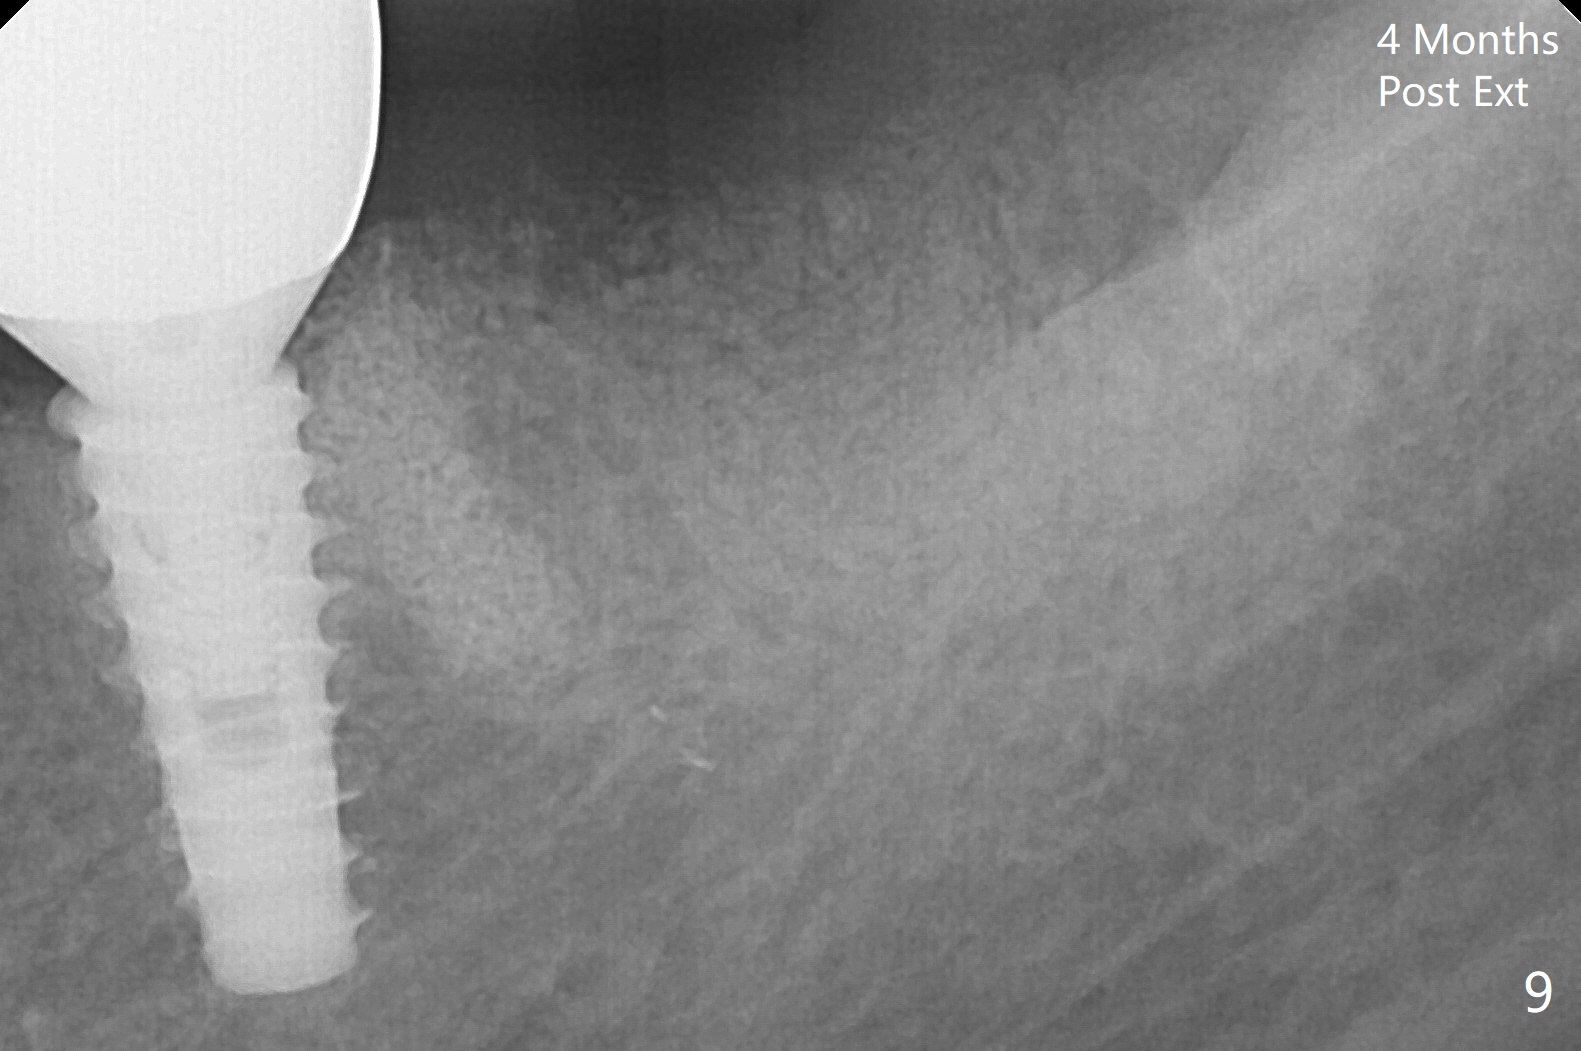

After making a 10 mm incision at the site of #19, #15c blade is used as an osteotome to start bone expansion, followed by Magic Split and Magic Expander (ME, 3 mm in diameter).  The depth is approximately the bottom of the mesial socket.  The osteotomy beyond the socket has to be done with 1.6 mm pilot drill (Fig.1) in combination of ME.  Following ME 4.3 mm and Magic Drill (MD) 3.8 mm for 15 mm (gingival level), a 4.5x11 mm dummy implant is placed with 50 Ncm (Fig.3); the implant looks narrow for the edentulous space.  After ME 4.8, MD 4.3 for 13 mm and Final Drill for 15 mm, a 5x11 mm IBS is inserted with >50 Ncm (Fig.3).  With 2 more turns of the implant, a 6.5x4(2) mm abutment is placed (Fig.4).  Periodontal dressing is applied around the abutment for additional retention.  A provisional is fabricated 3 weeks postop.  The provisional and abutment are loose 4 months postop (Fig.5).  After retightening the abutment, impression is taken for final restoration.  There is no bone loss 1 year 3 months post cementation (Fig.6).  After use of #100 file (Fig.7), the canal is debrided with #140 file with 1.5 mm shorter in working length with placement of Calcium Hydroxide paste.  Pain gets worse post RCT retreatment. There is limited native bone for primary stability when an immediate implant is placed (red dashed line: the superior border of the Inferior Alveolar Canal).  Prepare IS regular and extra wide kits and tissue-level implants (>5 mm).  Socket preservation may be done instead.  If the socket is large and the vein is not so small, prepare PRF.  In fact blood drawing fails.  When the tooth is extracted, it is sensitive to remove granulation tissue.  Socket preservation is done with Vanilla graft at #18 (Fig.8); there is ~3.5 mm bone between the bottom of the single socket and the Inferior Alveolar Canal (red dashed line).  The socket at #18 seems to have healed 4 months post extraction (Fig.19), but the bone height appears to have been reduced (compare Fig.10,11).  The buccolingual width is also decreased (Fig.12,13).  A 4.5 or 5.0x10 mm implant is appropriate for the site (Fig.14).  There is no bone loss at #19 (which may be associated with the bone expansion) 1.5 years post cementation (Fig.15).  Therefore the osteotomy at #18 will be assisted with bone expanders after 2.2 mm drill.